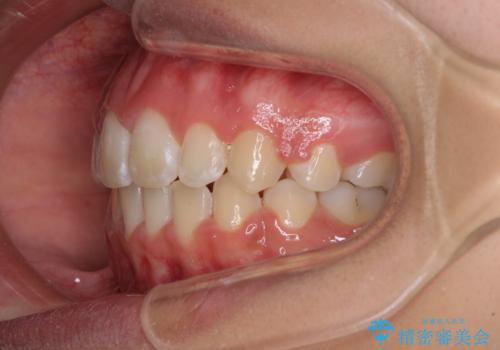

くちばしのように突出した前歯 口元を下げる抜歯矯正

口元を積極的に引っ込めるために、上下左右の第一小臼歯を4本抜歯することとしました。

前歯部の突出と開咬は、舌突出癖によるものでしたので、舌のトレーニングをしっかりと行っていただき、1年半程度と短期間で治療を終えることができました。